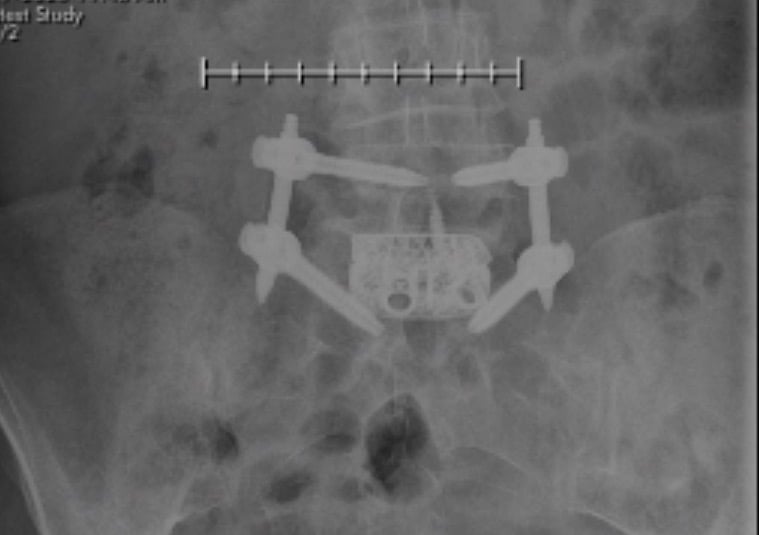

In September of 2015 I began having back and leg pain on my right side. As the pain got worse, I tried a chiropractor, then physical therapy. The pain kept getting worse so thinking that I had a hip problem, I made an appointment with my orthopedic surgeon at HSS. After x-rays and examination, Dr. Nestor determined that the problem was not my hip, but with my lower back and he referred me to a physiatrist, Dr. Wyss, also at HSS. We tried two epidural injections with no improvement. Although scheduling me for a third epidural, Dr. Wyss had the foresight to suggest that I consult with a back surgeon and recommended Dr. Cunningham.